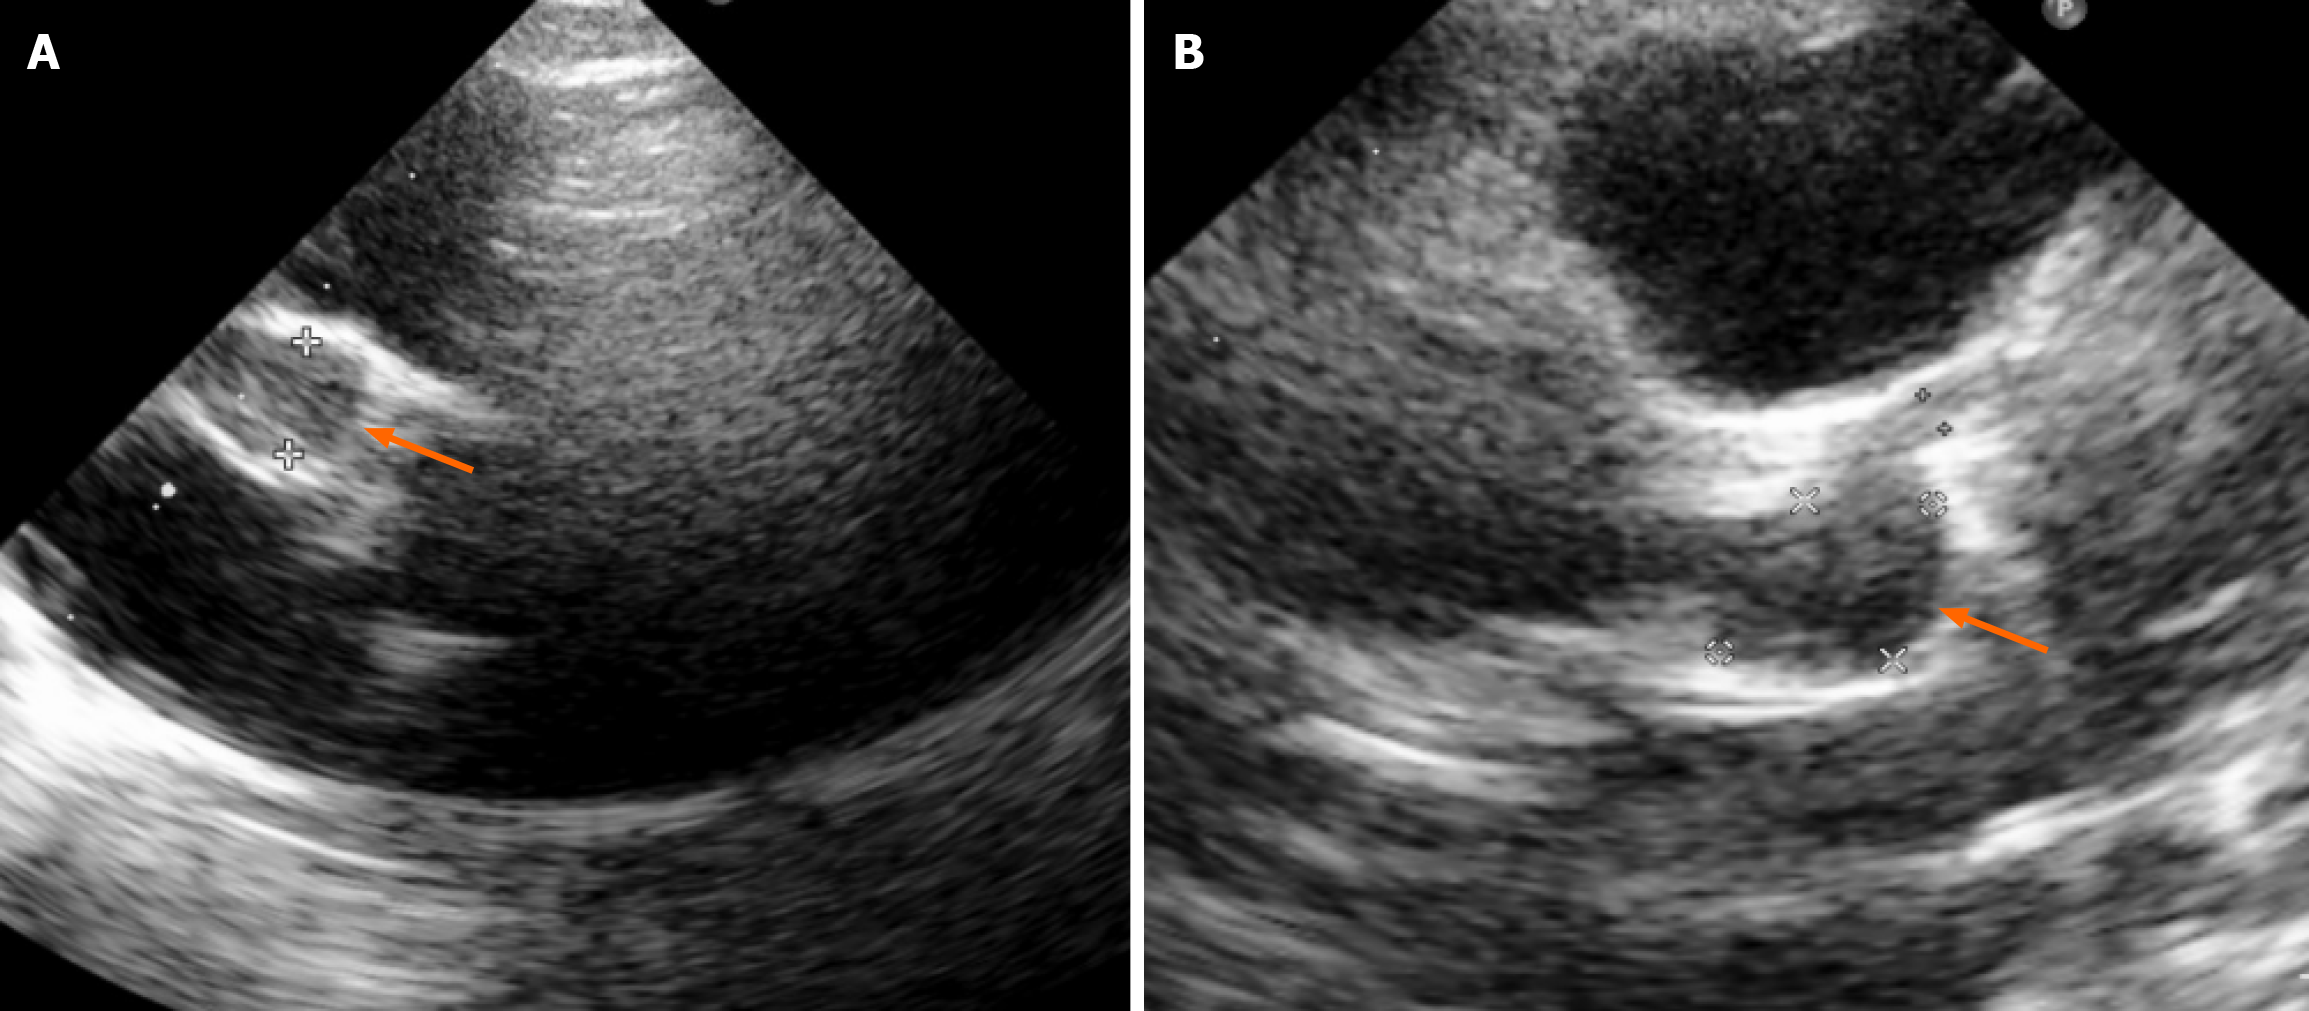

Figure 1 Bedside echocardiography demonstrating giant bilateral coronary artery aneurysms (indicated by orange arrows).

A: Right coronary artery aneurysm measuring 8.1 mm (Z-score = +19) with evidence of intraluminal thrombus; B: Left main coronary artery measuring 1.6 mm in diameter, and left anterior descending artery aneurysm measuring 7.5 mm × 10.3 mm (Z-score = +15).